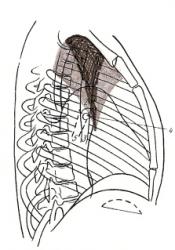

Ниже приведены схемы спадения долей и сегментов (по Anacker H., 1963) – иллюстрации 11, 12, 13.

Для своевременной диагностики, как долевых, так и сегментарных ателектазов необходимо уделять внимание следующему:

- положение и наличие деформации междолевых и межсегментарных щелей;

- степень спадения отдельных структурных единиц лёгкого;

- закономерности их перемещения при спадении;

- состояние окружающих тканей лёгкого;

- возможности перемещения диафрагмы, средостения и здорового лёгкого – иллюстрация 14.